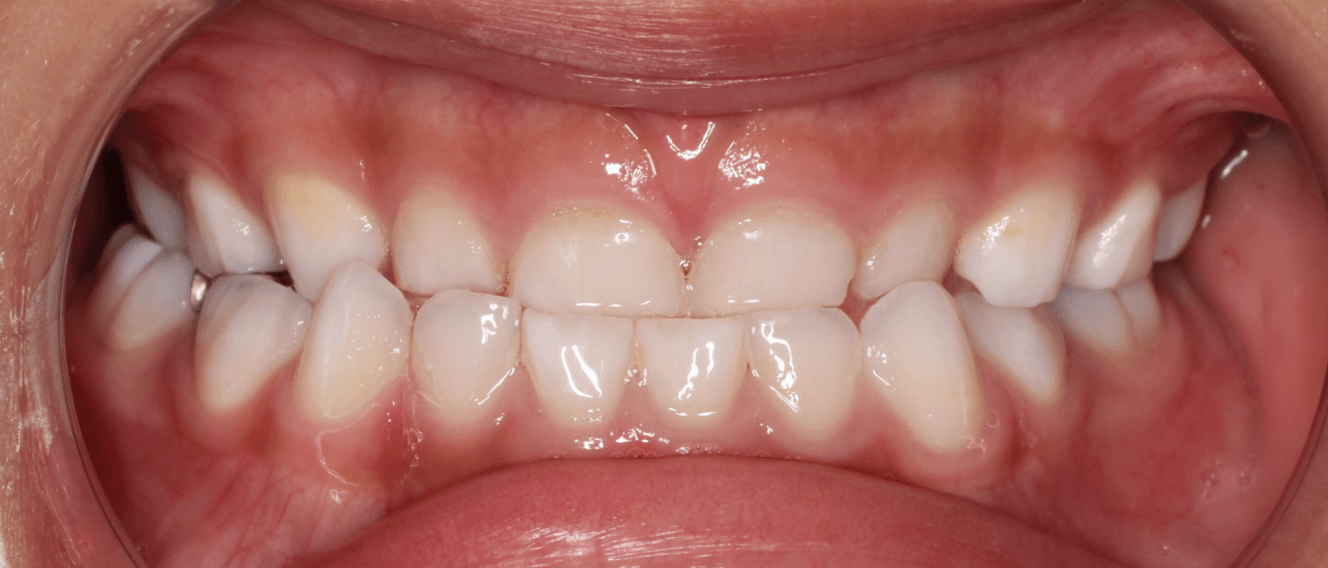

切端咬合位が取れるか

反対咬合は、前歯の位置異常が原因の場合は軽度であり、骨格の不調和が原因の場合は重度であることが多くなります。そこで受け口の治療難易度を調べる上で、上下の前歯を歯先で合わせる「切端咬合位」ができるかが重要な指標となります。

切端咬合位ができる反対咬合は、早期接触といって上下の歯をかみ合わせた際に奥歯より前歯が先に接触していしまうため、下あごを前に出てしまい受け口となってしまうメカニズムです。機能性反対咬合とも呼びます。

この場合は、前歯の位置以上が原因となっているため、準備矯正治療で前歯を移動させることで受け口の改善は可能です。奥歯が永久歯に生えかわる前に早期に矯正治療を開始することをお勧めいたします。

一方、どんなにあごを動かしても切端咬合ができないは、上下あご骨の長さの違いが原因となっている可能性があり難易度が高まります。レントゲン分析で下顎の相対的な長さを計測し、治療成功率を算出します。